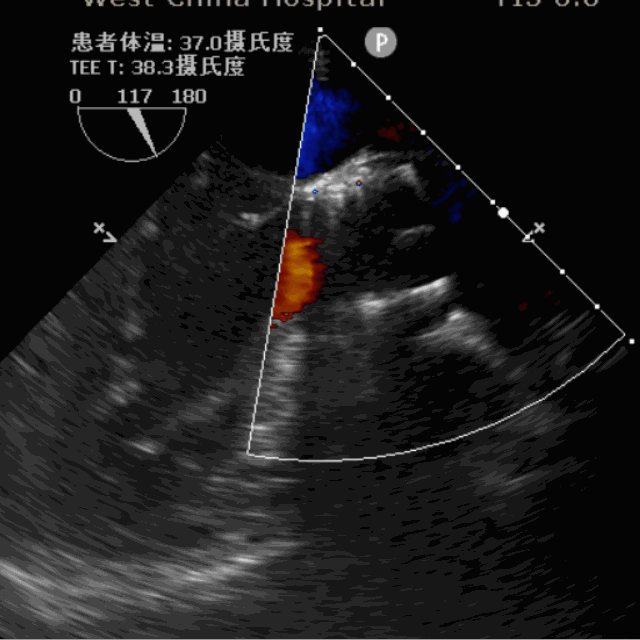

手术采用左侧心尖处微创手术切口,植入前用25mm球囊进行预扩1次,在DSA及超声引导下植入JS-TAVI 29#牛心包瓣膜,瓣膜释放后造影及TEE确认瓣膜位置及功能良好,采用25mm球囊后扩张1次,手术顺利完成。术前升主动脉根部测压114/41mmHg,左室压154/11mmHg,术后升主动脉根部测压109/50mmHg,左室压94/47mmHg。从导入器械到完成瓣膜置入,耗时8分钟,术中失血30ml,未输血。术后即刻主动脉瓣返流程度由术前大量返流转为消失,术后测得跨瓣峰值流速1.6m/s,平均跨瓣压差4mmHg,峰值跨瓣压差10mmHg。

术前超声影像图

术后超声影像图